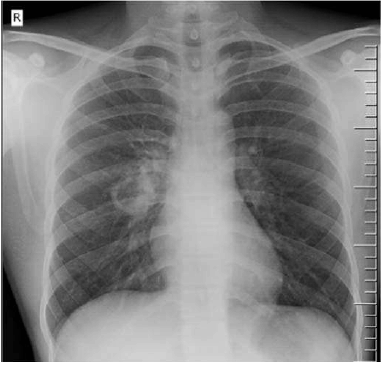

Paciente do sexo feminino, de 39 anos de idade, natural e procedente de São Paulo – SP, sem comorbidades, procura atendimento no Centro de Saúde Escola por quadro de perda ponderal de 8 kg em 4 meses, tosse produtiva, febre baixa no início da noite, fadiga e nodulações cervicais. Ao exame, revela-se emagrecida, descorada 2+/4+, afebril, com nodulações endurecidas em cadeias cervicais anterior e posterior, com ausculta cardíaca sem alterações e estertores crepitantes em ápice direito. Realizou a radiografia de tórax apresentada a seguir.

Com base nesse caso clínico, assinale, entre as alternativas a seguir, aquela que apresenta a principal hipótese diagnóstica do quadro pulmonar e seu exame confirmatório, respectivamente.